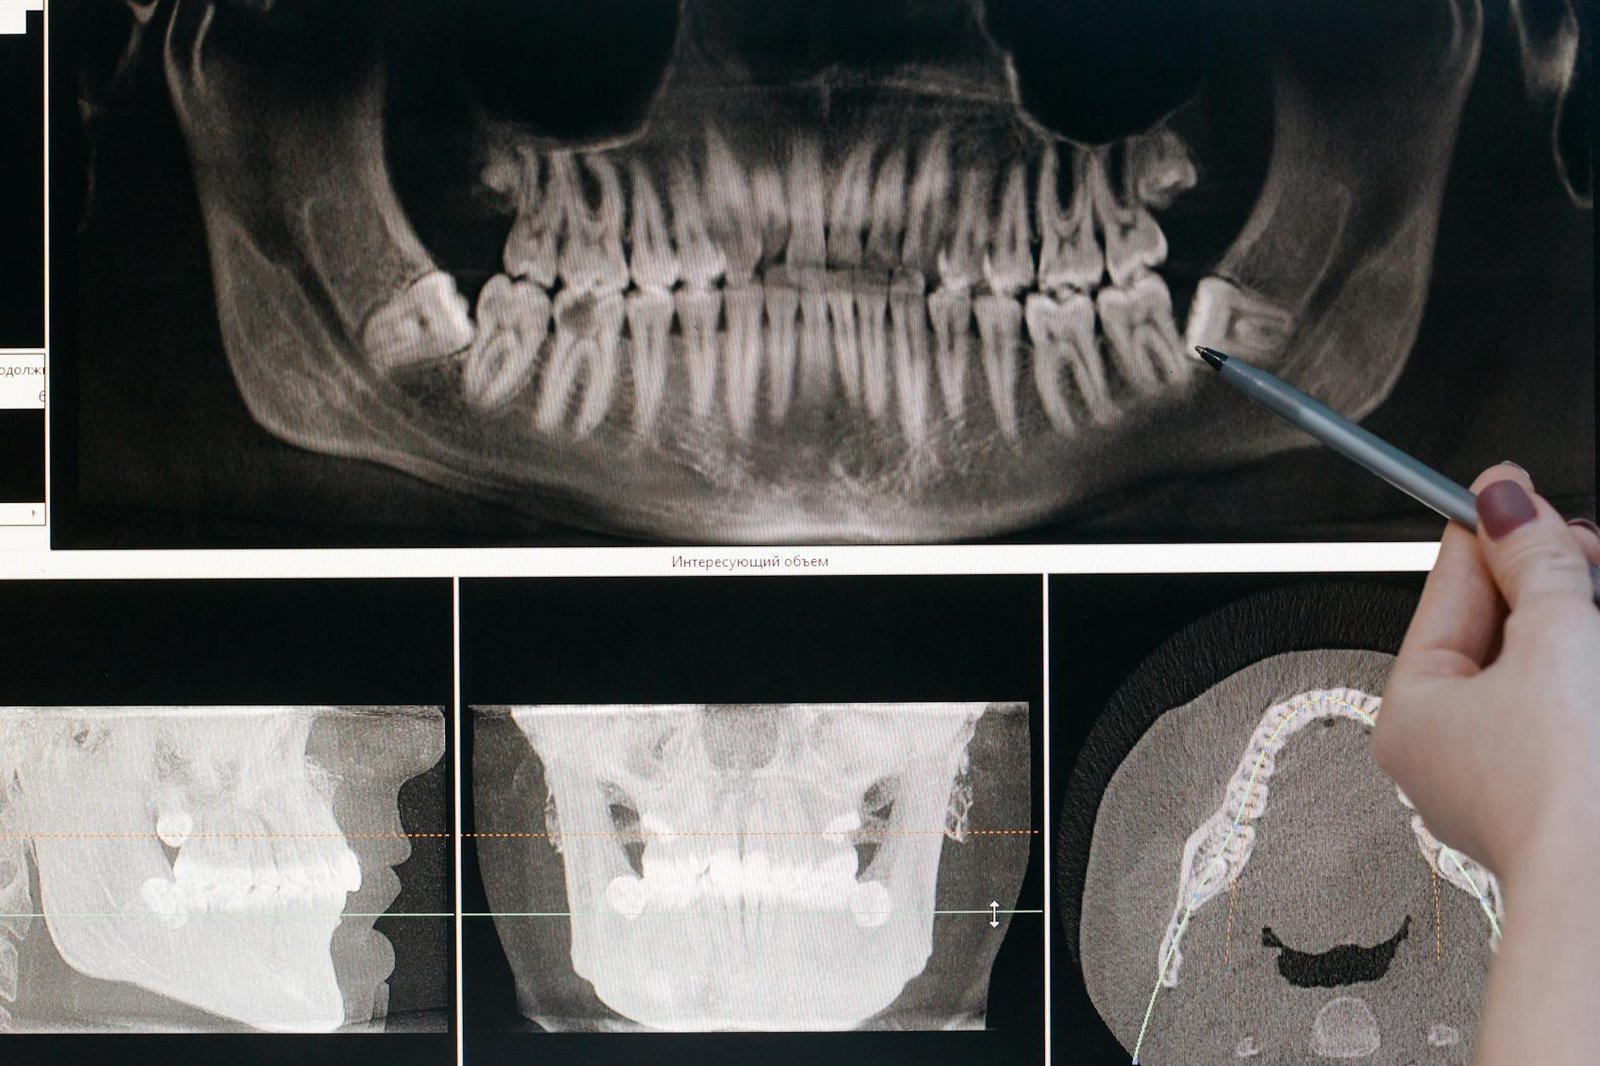

Cone beam CT imaging transforms the way dental professionals approach diagnosis by delivering complete three-dimensional visualization of oral and maxillofacial structures. Unlike conventional radiographs that compress anatomical structures into flat, two-dimensional images, CBCT provides volumetric data that can be manipulated and viewed from multiple angles and planes.

The technology works by rotating a cone-shaped X-ray beam around the patient’s head, capturing hundreds of individual projection images during a single scan. These images are then reconstructed by sophisticated software algorithms to create detailed cross-sectional views in axial, sagittal, and coronal planes. This comprehensive approach allows practitioners to examine structures that might be obscured or overlapped in traditional radiographic images.

CBCT’s ability to generate real-time cross-sectional views revolutionizes treatment planning accuracy across multiple dental specialties. The technology provides immediate access to axial, sagittal, and coronal sections, allowing practitioners to evaluate anatomical relationships and pathological conditions from multiple perspectives during patient consultations.

Implant treatment planning exemplifies CBCT’s real-time advantages most dramatically. Practitioners can measure bone dimensions, evaluate bone quality, and identify critical anatomical structures like the inferior alveolar nerve or maxillary sinus in real-time during the planning session. Interactive software allows for virtual implant placement, enabling clinicians to optimize positioning, angulation, and depth before surgery begins. This real-time capability reduces surgical time, improves outcomes, and enhances patient confidence through visual treatment presentations.

Implant Site Assessment

CBCT imaging has become the gold standard for implant site evaluation, providing essential information about bone volume, density, and anatomical limitations. The technology enables precise measurement of available bone height and width, allowing practitioners to select appropriate implant dimensions and plan optimal placement positions.

Anatomical Structure Identification

Critical anatomical structures like the inferior alveolar nerve, mental foramen, and maxillary sinus become clearly visible on CBCT scans. This visualization enables safe implant placement by helping practitioners maintain appropriate safety margins from vital structures. The ability to trace nerve pathways and assess sinus pneumatization patterns reduces the risk of surgical complications and improves treatment predictability.